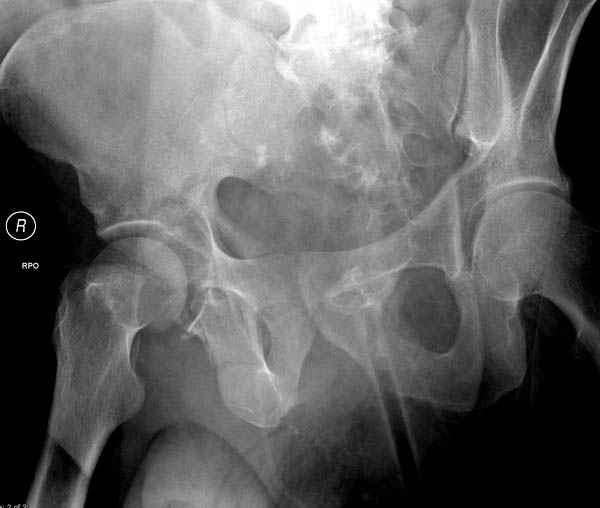

По возможности вышлите снимки, сканы таза до

реконструкции, интраоперационные.

По снимку создается впечатление о высоком поперечном переломе, задней колонны, стенки; почему не пользовались *magic screw*?

Положение больного на животе или на боку?

Латеральное положение облегчает проведение тракции через вертел, за 5 мм стержень за вертел (грузом через тракционное приспособление), на обычном рентгенопрозрачном операционном столе, а для положения на животе, наверное, Judet Table более приемлем, потому что там имеется латеральное тракционное устроиство.

Там множество обычных 2.7 мм шурупов, потом идет фиксация основными пластинами.

Полную нагрузку разрешаем в 12 недели, хотя движения в суставе с первых дней.

Снимки здесь....